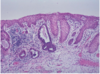

descrbe the histology of CIN I?

basal 1/3 of epithelium occupied by abnormal cells

*raised numbers of mitotic figures in lower 1/3

*surface cells quite mature, but nuclei slightly abormal

describe the histology of CIN II?

abnormal cells extend to middle 1/3

*mitoses in middle 1/3

*abnormal mitotic figures

describe the histology of CIN III?

abnormal cells occupy full thicknes of epithelium

*mitoses, often abnormal, in upper 1/3